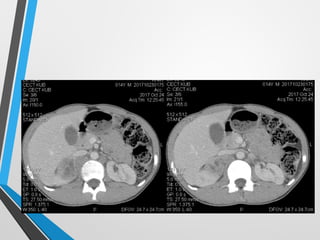

CECT scan as next imaging modality

• A well outlined about 4.5x4.5cm heterogeneously

CECT scan asnext imaging modality • A well outlined about 4.5x4.5cm heterogeneously enhanced mass at right suprarenal region • Two small nodular lesion about 2.5x2.o cm ,0.5x0.5 cm in right renal hilum minimally compressing and displacing right renal vein • Another hyperdense markedly enhanced about 4.5x2.5 cm mass lesion at left suprarenal region • Wash out effect in delayed film • Normal functioning both kidneys, ureter and bladder •

• 16.

hyperdense markedly enhancedabout 4.5x2.5 cm mass lesion at left suprarenal region